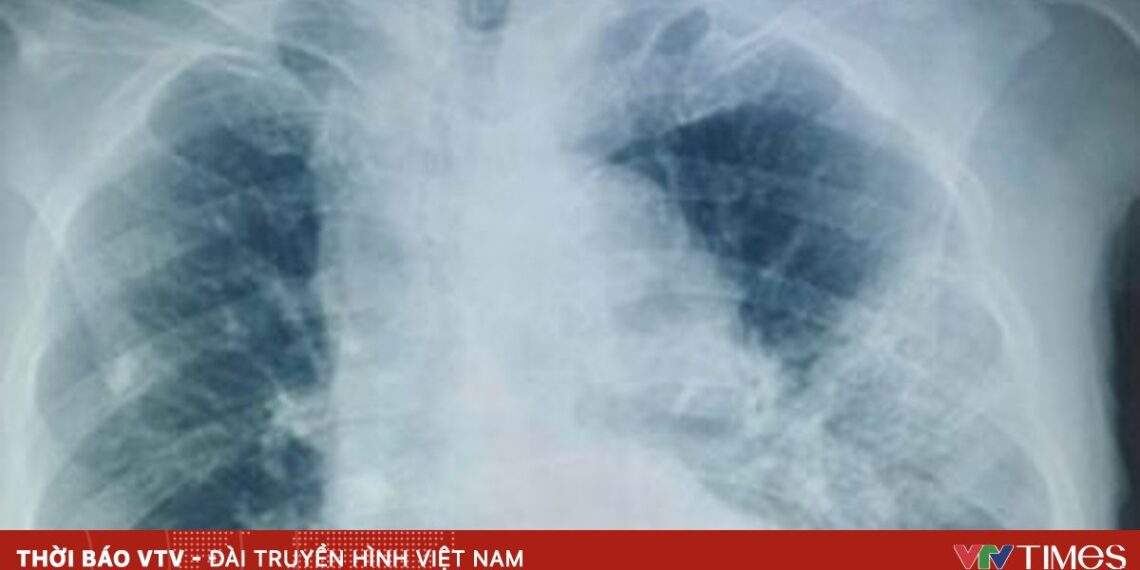

Trong quá trình điều trị, bệnh nhân diễn tiến nặng nhanh với suy hô hấp, sốt dao động 39-40 độ C và đáp ứng kém với phác đồ kháng sinh phổ rộng (piperacillin/tazobactam phối hợp levofloxacin). Trước tình trạng lâm sàng không cải thiện, bệnh nhân được nội soi phế quản. Kết quả cấy dịch rửa phế quản sau 5 ngày nhập viện cho thấy Candida albicans.

Candida albicans là nấm men thường trú ở niêm mạc miệng – hầu họng, thường không gây bệnh khi cơ thể khỏe mạnh. Tuy nhiên, ở người cao tuổi, suy giảm miễn dịch hoặc sử dụng kháng sinh phổ rộng kéo dài, nấm có thể gây nhiễm trùng xâm lấn, trong đó viêm phổi là thể bệnh khó chẩn đoán do biểu hiện lâm sàng và hình ảnh học không đặc hiệu.

Chẩn đoán xác định nhiễm Candida xâm lấn cần dựa vào cấy nấm dương tính từ các bệnh phẩm vô khuẩn hoặc mô bệnh học. Trên lâm sàng, cần nghĩ đến căn nguyên nấm khi bệnh nhân viêm phổi nặng, sốt kéo dài, không đáp ứng kháng sinh sau 4-7 ngày, đặc biệt ở nhóm nguy cơ cao.